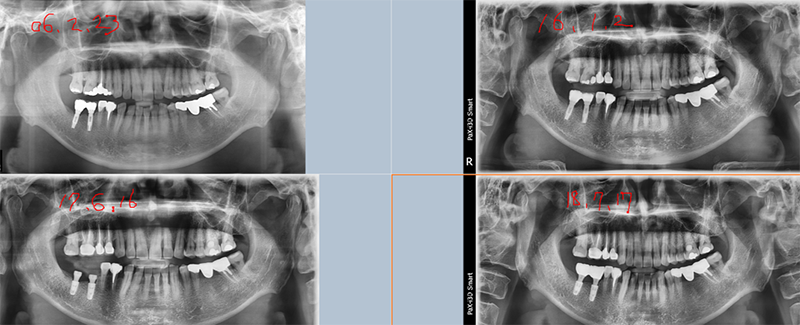

37번 4.3 직경의 원플란트

제거하다가 흠집이 날 것 같아서 포기하고

다음에 약속 잡았는데 환자도 저도 미루다가 이 지경됨.

파노라마 상

결국 픽스쳐 제거

아마도 교합에 문제가 있었던 듯

37번 abutment 파절, 뒤쪽에 8번이 보이고, fixture 직경이 5.0, 조금 흠집이 나도 된다는 생각으로 제거수술을

했다.

3번에

나눠서 겨우 제거한 경우